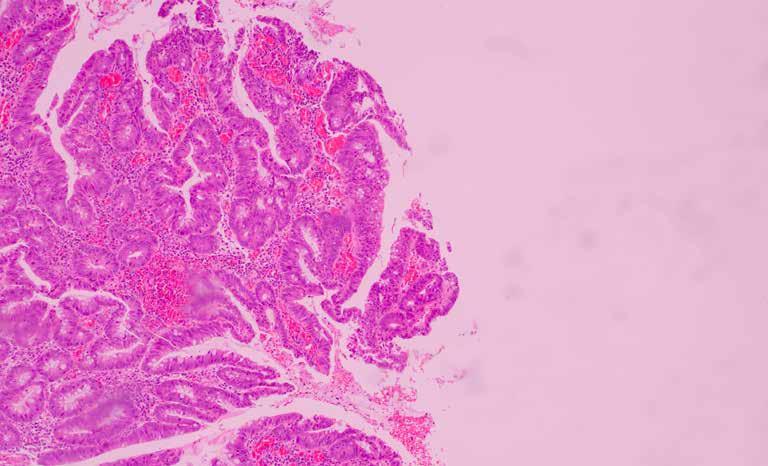

sembrano influenzare e favorire l’emergere di tumori al seno sono il sovrappeso, l’obesità e il consumo di alcol, mentre l’allattamento al seno riduce i rischi. Esistono vari tipi di tumori al seno. I più diffusi sono i carcinomi, originati da cellule epiteliali, che possono essere duttali ((70-80% circa del totale, sviluppatisi dalle cellule dei dotti), lobulari (1015%, originati dai lobuli), tubulari, papillari, mucinosi e cribriformi, meno comuni e con prognosi generalmente favorevole.

© sergey kolesnikov/shutterstock.com